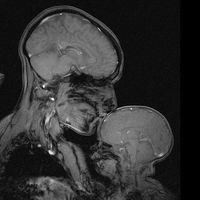

¡Juega con tu bebé! Al jugar juntos, sus cerebros se sincronizan y comienzan a "comunicarse" entre ellos

DesarrolloEstudiar cómo funciona el cerebro del bebé es algo que siempre nos ha fascinado, pues resulta increíble ver lo mucho que crece, aprende y logra durante sus primeros días y meses de vida. Un tema que además interesa a los científicos, son...